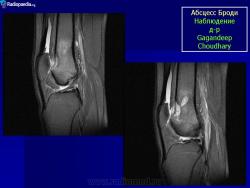

Рентгенологически обнаруживают полость с чёткими склерозированными контурами, при обострении периостальные наслоения, остеосклероз.

Рис. 208. Хронический костный абсцесс Броди в верхнем метафизе большеберцовой кости.

Рис. 207. Хронический костный абсцесс Броди у 22-летнего больного. Болен 7 лет, периодически боли в коленном суставе и „симпатический” перемежающийся экссудативный гонит. Оперативное и гистологическое подтверждение диагноза.

Характерен для абсцесса Броди значительный остеосклероз губчатого вещества, окружающего полость, и лишь очень редко гнойник лежит среди нормальной спонгиозной ткани. На поверхности кости периостальные наслоения очень незначительны, так что если вообще имеется цилиндрическое или, скорее, веретенообразное утолщение метафиза на уровне гнойника, то только в самой умеренной степени. Как правило, секвестрации не бывает. До прорыва наружу или в полость соседнего сустава, несмотря на его близость, дело доходит лишь в редчайших случаях.

Рентгенологическое исследование имеет решающее диагностическое значение. Все детали патологоанатомической картины абсцесса Броди передаются в точности и на рентгеновских снимках (рис. 207 и 208). Изолированная, правильной округлой формы полость, без секвестра, с резко ограниченными гладкими внутренними контурами, расположенная среди склерозированного губчатого вещества, на типичном месте — в метафизарном конце большой трубчатой кости, слегка утолщенной благодаря периостальным наслоениям, — эта рентгенологическая картина при поддержке клинических симптомов разрешает диагностическую задачу. При этом следует учесть, что между, так сказать, классическим типичным абсцессом Броди и другими формами хронического остеомиелита бывают и переходные формы — и по местоположению, размерам, форме, характеру реактивных изменений в окружности, секвестрации и т. д. Это ведь в природе вещей: классификация показывает всегда несколько условно типичное, жизнь преподносит многообразие, не укладывающееся в строгую жесткую схему. Никоим образом не следует злоупотреблять диагнозом абсцесса Броди и ставить его расширительно, чуть ли не во всех случаях более или менее ясно выраженной полости при обычном хроническом остеомиелите: абсцесс Броди — это совершенно определенное клинико-рентгено-анатомическое понятие, это четкая нозологическая единица, и диагноз оправдан лишь в тех случаях, когда рентгенологическая картина удовлетворяет всем вышеперечисленным критериям.